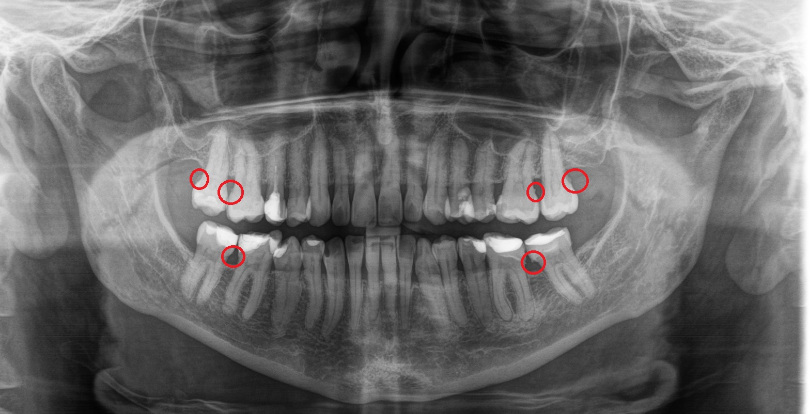

Diagnoza przedzabiegowa oparta o zdjęcie pantomograficzne zlecone przez stomatologa ujawniła dużą ilość kamienia poddziąsłowego - prawdopodobnie nigdy wcześniej nieusuwanego.

Ścisła współpraca z Lekarzami, weryfikacja RTG oraz technologia, w tym narzędzia do skalingu poddziąsłowego pozwoliły na zaplanowanie i wykonanie higienizacji na najwyższym poziomie i usunięcie złogów będących u Pacjentów przyczyną paradontozy.